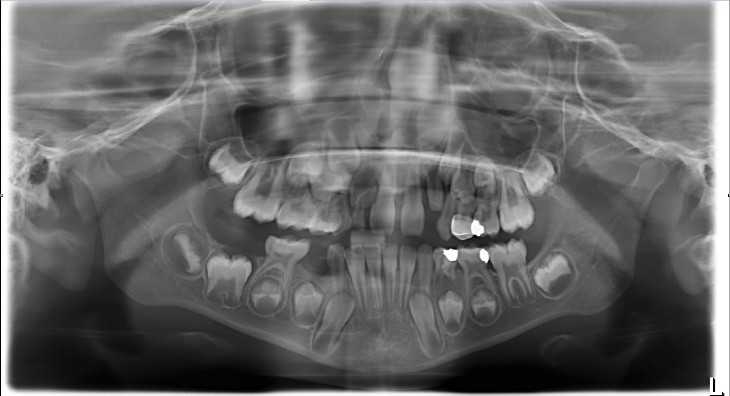

Which of the following may complicate the extraction of tooth 7.4?

Tooth 4.8 is planned for extraction. Which radiographic findings suggest an increase in the degree of difficulty of the extraction?

Tooth 2.8 is planned for extraction. Which radiographic findings suggest an increase in the degree of difficulty of the extraction?

Tooth 1.8 is planned for surgical extraction. Which radiographic findings suggest an increase in the degree of difficulty of the extraction?

Tooth 2.8 is planned for surgical extraction. Which radiographic findings suggest an increase in the degree of difficulty of the extraction?